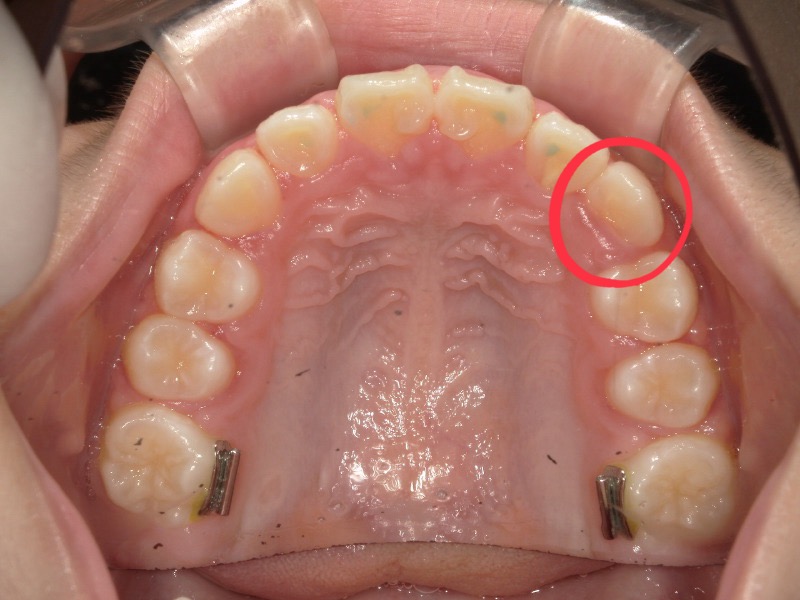

初診の写真を見ると前歯はある程度並んでいますが2番目の歯は斜めに生えており下からの写真では丸いアーチというより平坦のアーチになっています。

2番目の歯並び

スタートから一年後の歯並びです。

初めは平坦気味だった2番目の歯もアーチに沿って綺麗になっています。

ですがまだ生え変わりがあることと、スペースに余裕はないため装置を装着しました。

歯と歯にしっかりと隙間ができて広がっています。

装置をつけると一時的に出っ歯っぽく見えていますがここからまた上顎は変わっていきます。

2度目の装置

一度装置は外して様子を見ていたのですがまだスペースが欲しいため再度装置をつけました。

丸で囲っている歯が綺麗に入ることを目的とした装置にもなります。

装置が外れる頃には丸で囲った歯は綺麗に並んでいます。